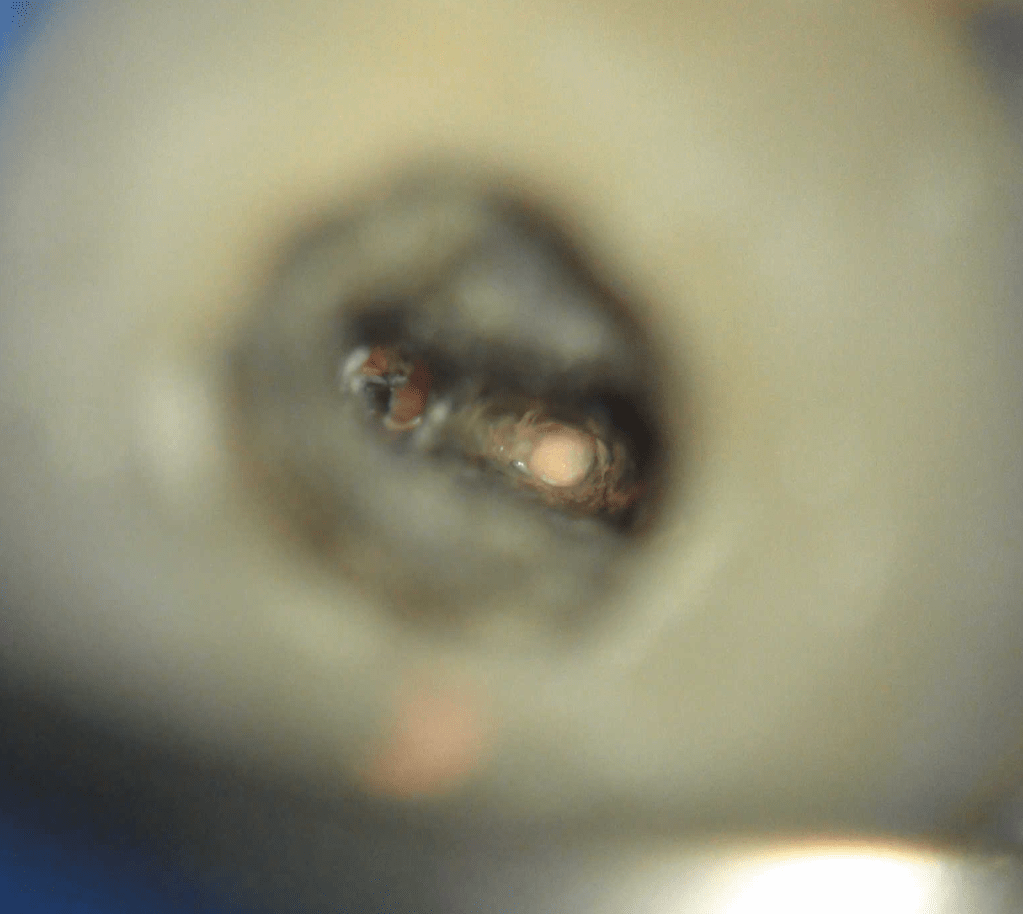

Remoción 2 Postes Moscados